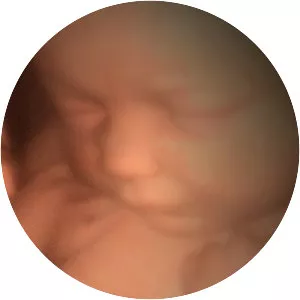

In The Womb photograph

Ultrasound imagery sheds light on the development of a foetus.